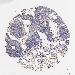

LUNG ADENOCARCINOMA (TCGA) - Interactive survival scatter ploti

The Survival Scatter plot shows the clinical status (i.e. dead or alive) for all individuals in the patient cohort, based on the same data that underlies the corresponding Kaplan-Meier plots. Patients that are alive at last time for follow-up are shown in blue and patients who have died during the study are shown in red.

The x-axis shows the expression levels (FPKM) of the investigated gene in the tumor tissue at the time of diagnosis. The y-axis shows the follow-up time after diagnosis (years). Both axes are complimented with kernel density curves demonstrating the data density over the axes. The top density plot shows the expression levels (FPKM) distribution among dead (red) and alive patients (blue). The right density plot shows the data density of the survived years of dead patients with high and low expression levels respectively, stratified using the cutoff indicated by the vertical dashed line through the Survival Scatter plot. This cutoff is automatically defined based on the FPKM cutoff that minimizes the p-score. The cutoff can be changed by dragging the vertical line or by entering a cutoff value in the square labeled "Current cut-off".

Under the Survival Scatter plot the p-score landscape (black curve; left axis) is shown together with dead median separation (red curve; right axis). Dead median separation is the difference in median mRNA expression between patients who have died with high and low expression, respectively. It is calculated as follows: median FPKM expression of dead patients with high expression - median FPKM expression of dead patients with low expression. This is intended to aid the user in visually exploring custom cutoffs and the associated p-scores and dead median separation.

Individual patient data is displayed and can be filtered by clicking on one or more of the category buttons on the top of the page. Categories describing expression level and patient information include: high, low, alive, dead, female, male and tumor stages. The scale of the x-axis can be toggled between linear and log-scale by clicking on the "x log" button. Mouse-over function shows TCGA ID, patient information and mRNA expression (FPKM) for each patient.

& Survival analysisi

Kaplan-Meier plots summarize results from analysis of correlation between mRNA expression level and patient survival. Patients were divided based on level of expression into one of the two groups "low" (under cut off) or "high" (over cut off). X-axis shows time for survival (years) and y-axis shows the probability of survival, where 1.0 corresponds to 100 percent.

LRG1 is not prognostic in Lung Adenocarcinoma (TCGA)

: 40.87